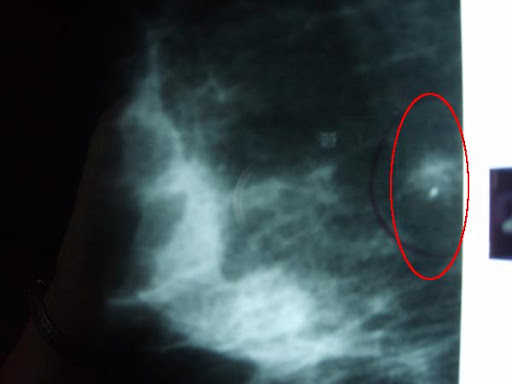

Yes, I was 6 months late getting my mammogram, but I had no pain, no lumps, no family history, and no reason to be concerned. Until I saw that Right CC. There, next to my chest wall on the inside of my right breast was a star-shaped lesion with a large calcification in the center. That same lesion was evident on the RMLO (right medial-lateral obligque image–the one taken from the side.) But it was the Friday before Father’s Day and the radiologist had already gone home. So, I had all weekend to worry about that lesion. And suddenly, I had a BIG reason for concern. I’m not a doctor or radiologist, but I’d seen enough mammograms and enough cancers in my time to know that lesion didn’t look good.